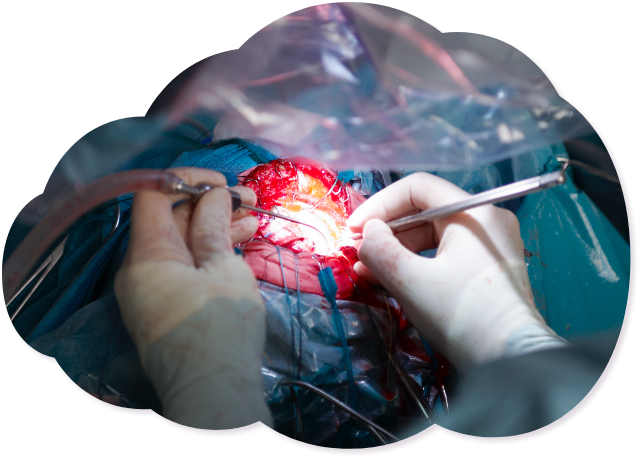

Surgical Interventions

Depending on the severity of the disease, one to three surgical sessions are necessary, each lasting four to eight hours. In this surgery the blood flow to the brain is enabled by performing a bypass circuit constructed from the patient's scalp vessels and cortical arteries lying on the surface of the brain (resvacularization surgery).